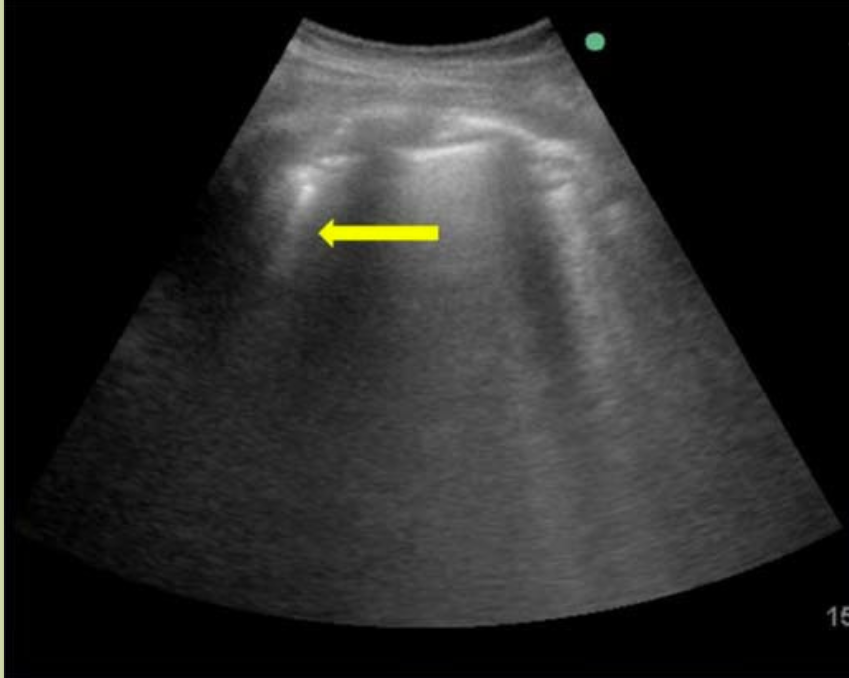

胸腔积液

为脏层与壁层胸膜之间的无回声暗区,合并压缩性肺不张时,可出现「海蜇征」或「舌头征」